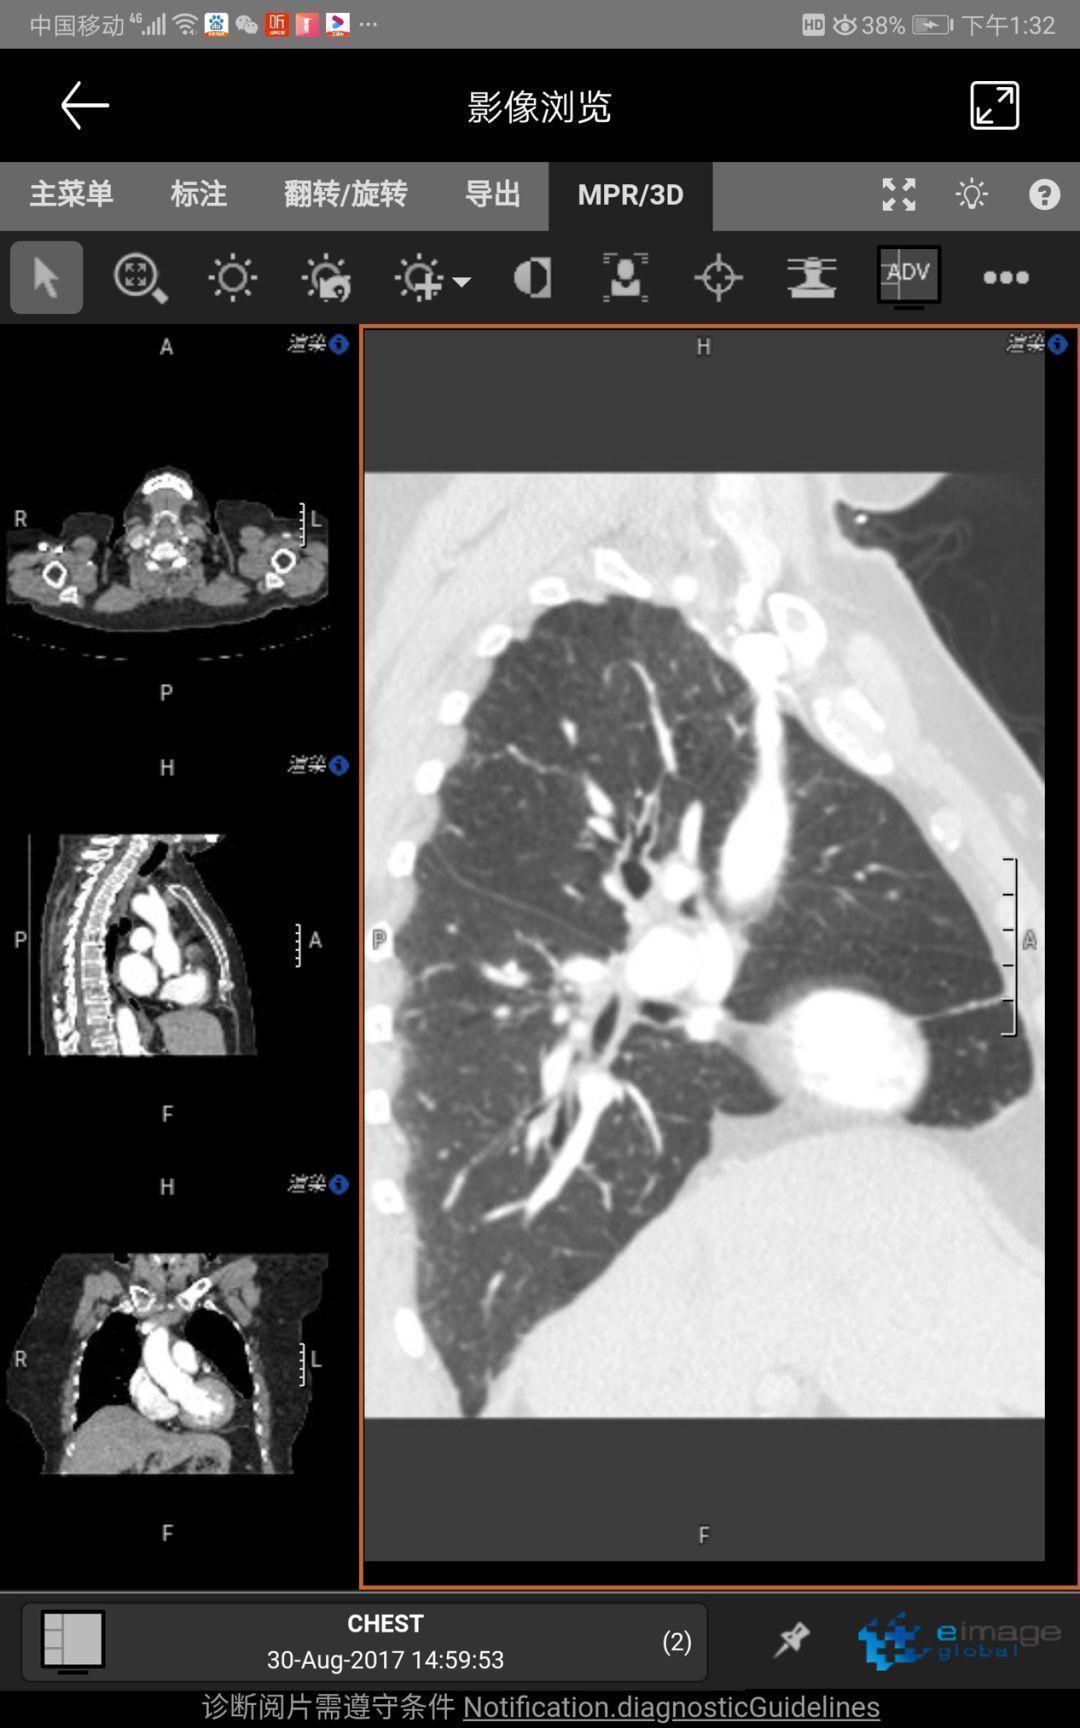

As a branch of eimagelobal.com, the COVID-19 platform integrated a powerful web based DICOM viewer, especially for Lung CT scan images. The MPR and Slice thickness adjustment will help radiologist and pulmonologists to read with greater ease and accuracy.

作為全球影(ying)像(xiang).com的定制化(hua)平臺,國際(ji)平臺集成了功能強大的DICOM影(ying)像(xiang)處理軟(ruan)件,尤其(qi)對于肺(fei)部CT掃描影(ying)像(xiang),MPR和(he)層厚調節(jie)功能讓(rang)影(ying)像(xiang)醫生和(he)肺(fei)科醫生更容(rong)易、更準確(que)地閱片(pian)。